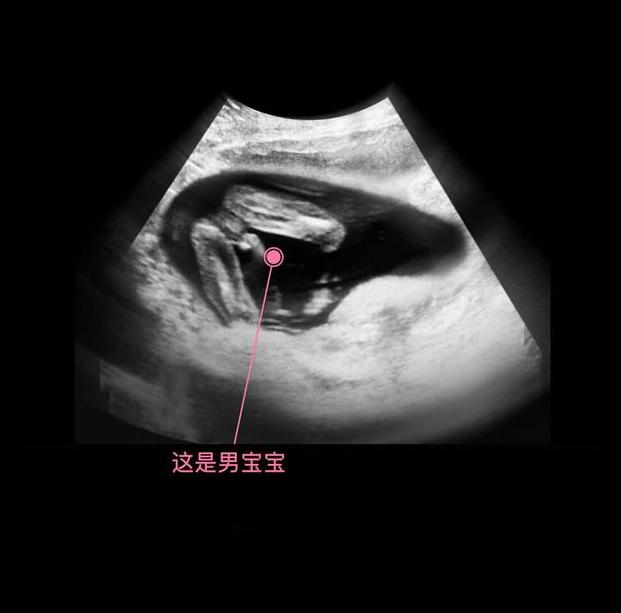

进入了16周,胎儿具备了很多本领,比如吞咽羊水、排出尿液、玩耍脐带、开始有了妈妈能够感受到的胎动,胎儿生殖器官的发育开始可见。

其实从孕9周开始,胎儿的性别就开始分化,孕17周,B超扫描清晰可见胎儿的性别,不过也有的宝宝因为胎位的原因,或者脐带遮挡,让医生产生了误判,男女会出现翻盘的可能呢。